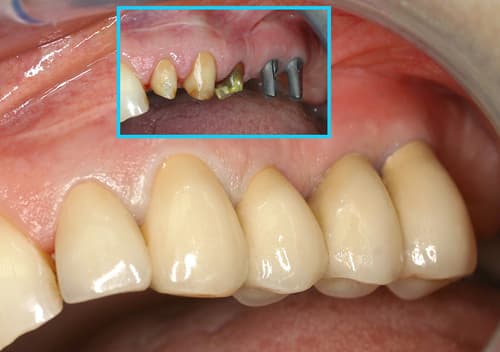

Pré-opératoire